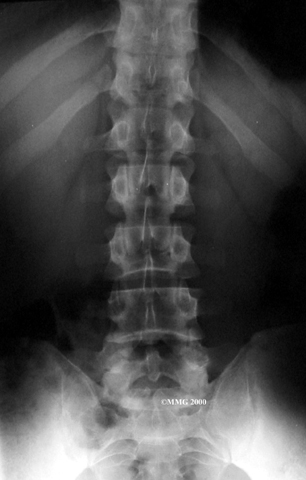

Physician Review

are of minor help in diagnosing disc herniations. The discs don't actually show up on X-rays. However, doctors can tell if the space between the vertebrae is smaller than normal. This can be an indication that wear and tear on one or more discs is causing problems. However, many peoples' X-rays show degeneration of the discs. This is because degeneration in the discs is part of aging, like skin that wrinkles with time.